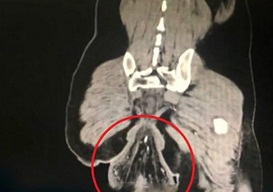

Окуя Кытайдын Чжуншань шаарында Гуандун аймагында орун алган. Унитазда көпкө олтурган жигит “кызыктай нерсенин” чыкканын байкаган. Ооруканада жаткан жигит адатта дааратканада уюлдук телефондон көп оюн ойногондуктан, узак олтурарын айткан. Ал эми дарыгерлер “уюган нерсе” жигиттин көтөн чучугу экенин аныкташкан.

Дарыгерлердин айтымында, көтөн чучуктун түшүп калышы унитазда көп олтургандан болушу мүмкүн. Жигиттин ден соолугун көзөмөлдөгөн дарыгердин айтуусу боюнча, бир нече жыл мурда анын ден соолугунда көйгөйлөр жаралган. Бирок, тийиштүү деңгээлде дарыланбагандыктан, оорусу өтүшүп кеткен. Азыркы убакта ысымын жашырууну туура көргөн жигит дарыланып жатат.